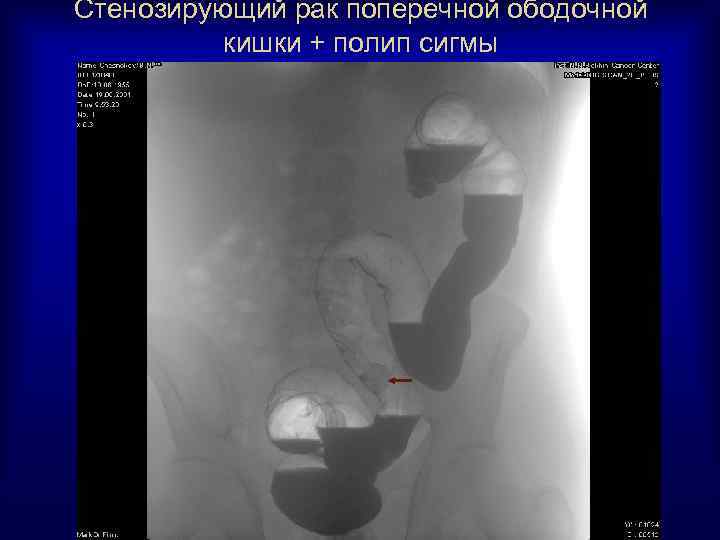

Стенозирующий рак поперечной ободочной кишки + полип сигмы